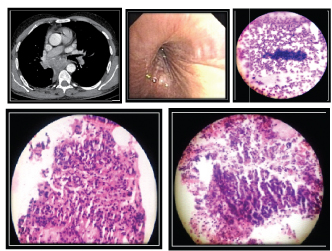

Case 1 shows a left hilar mass which showed a presence of an endobronchial growth on bronchoscopy. Diagnosis was confirmed with forceps biopsy showing small cell. [Table/Fig-9] shows visible cell pellet after centrifuging bronchial washings which were used to prepare smears and CB. CB of bronchial washings was positive for malignancy in this case where corresponding bronchial washings smear was negative for malignancy.

(a) CECT- Thorax showing left Hilar mass. (b) Bronchoscopy showing presence of an endobronchial growth. (c) Visible cell pellet after centrifuging washings (d) Biopsy positive for Small cell Carcinoma (e) Bronchial washings cellblock positive for Small cell carcinoma (f) Bronchial washings smear negative for Malignancy